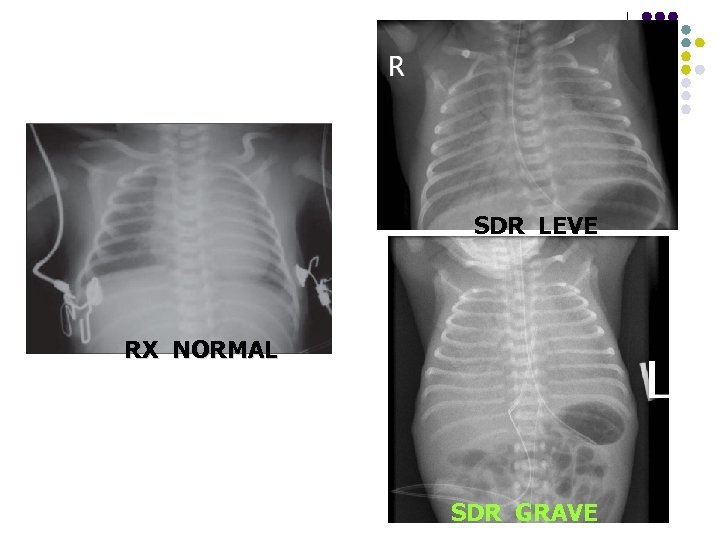

SDR LEVE RX NORMAL SDR GRAVE